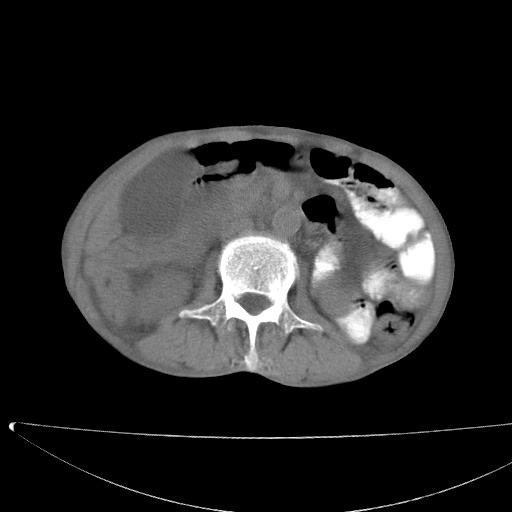

标题: CT17147:男70岁,上腹部不适1月。 [打印本页]

患者男70岁,上腹部不适1月。8年前有胃癌手术史。余病史不祥。

1)胃癌术后,不排除复发可能。2)考虑肝脏及腹膜后淋巴结转移瘤。3)肝内胆管扩张,胆囊增大。4)肝内胆管结石(或钙化)。5)脾脏钙化灶。6)腹水。7)右侧少量胸腔积液。

建议:行ct增强扫描检查。